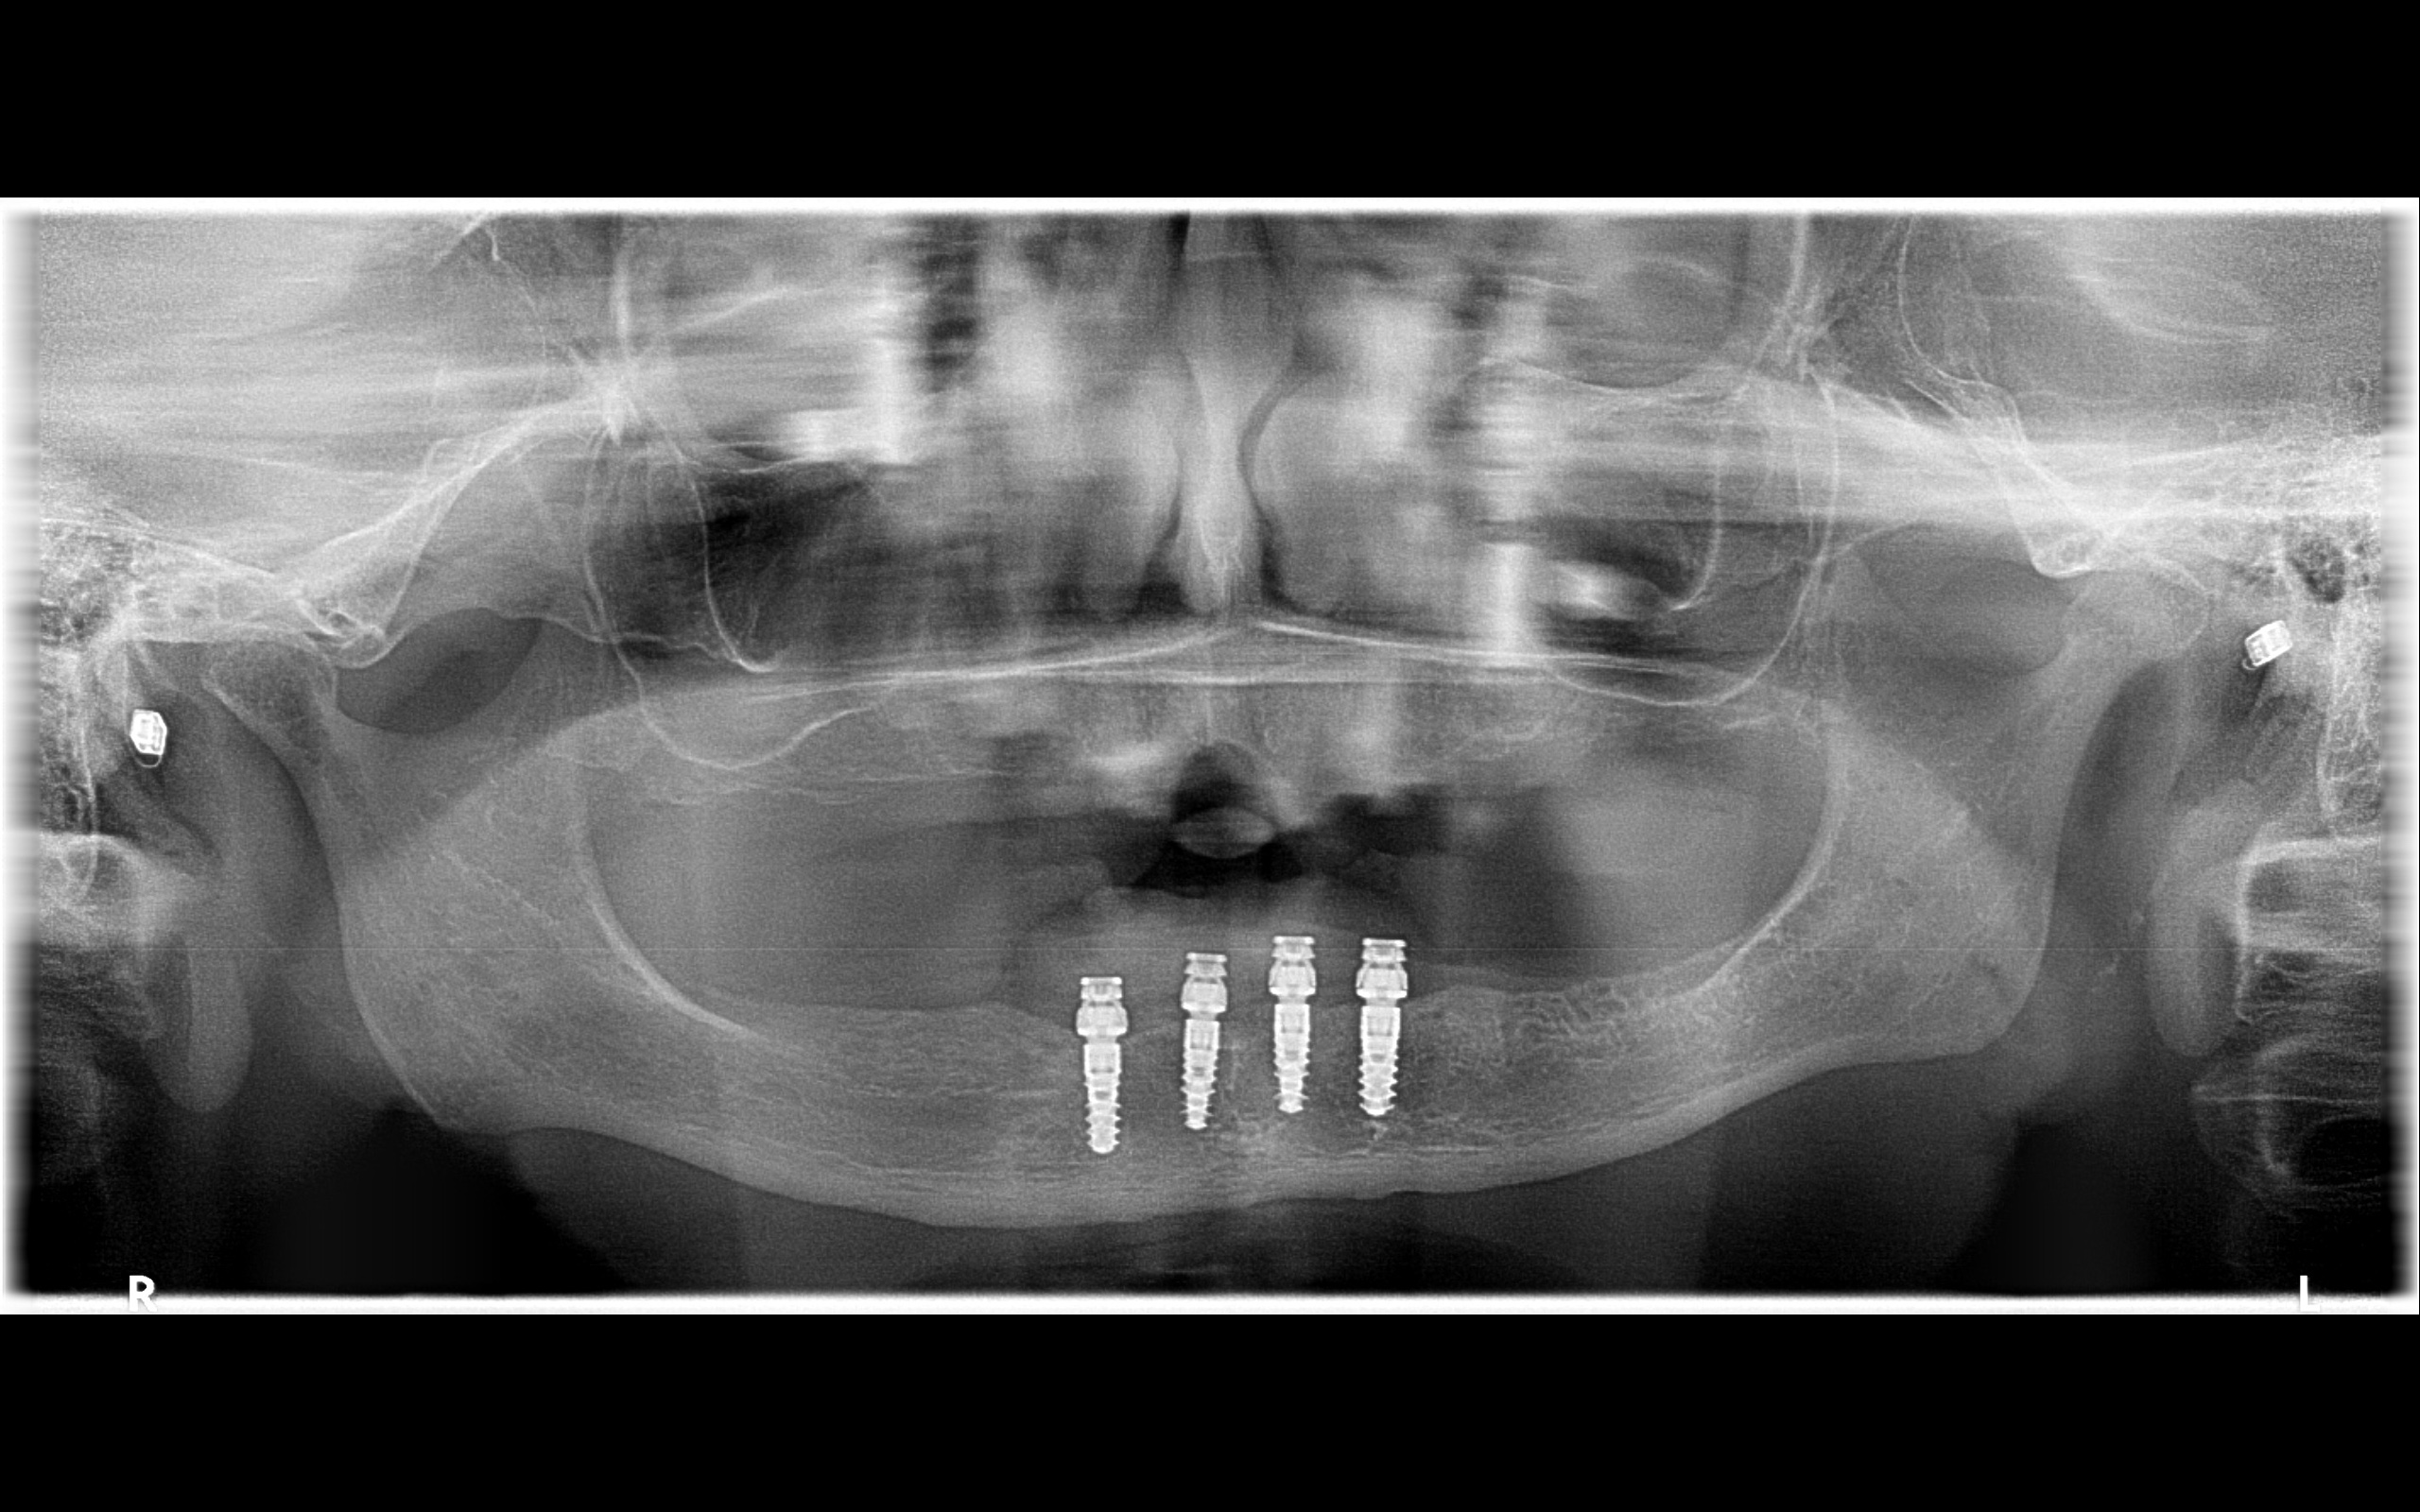

歯を失うと、その部位の骨は徐々に痩せていきます。さらに上顎洞は時間とともに下方へ広がる性質があり、結果として骨の高さが減少します。例えば上顎6番の部位で残存骨が2〜3mmしかない場合、通常使用される8〜10mm程度のインプラントは安定しません。

初期固定とは、埋入直後にどれだけしっかりと骨に締結されているかを示す指標です。残存骨が1〜2mmでは、この初期固定が得られません。そのため、まず骨造成を行い、約6か月の治癒期間を経てからインプラントを埋入する計画になります。

重要なのは術式の名前ではなく、骨量と咬合設計に基づいた判断です。サイナスリフトの適応は、CTによる三次元診断なしには決定できません。